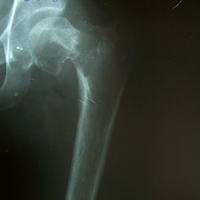

Case:4 Post Tuberculous Ankylosed Hip

Pre-op

Post-op